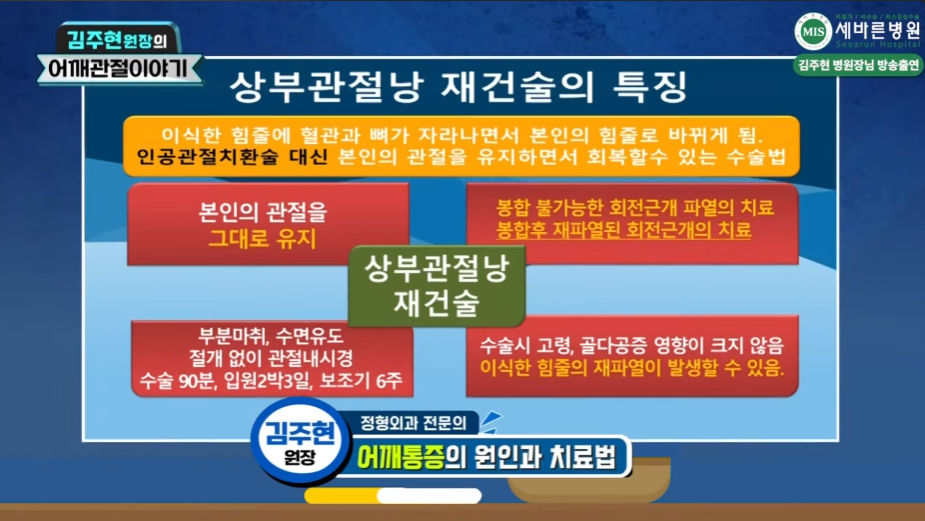

오늘 서초동 정형외과 세바른병원에서 회전근개 재파열 어깨 재수술로 적용할 수 있는 치료법인

상부관절낭재건술치료방법에 대해 알아보도록 하겠습니다.

이제는 의료기술의 발달, 첨단 의료기기의 보급으로 인해 회전근개 재파열 또는 어깨힘줄이 완전히 다 끊어져서 팔을 못 들어 올리는 환자분들도 ⭐마지막 단계인 인공관절 수술을 하지 않고도 내시경을 이용하여 자기의 관절을 그대로 사용할 수 있는 치료방법이 고안되었습니다. 바로✅상부관절낭재건술이라고 하는 방법인데요. 지금부터 알아보겠습니다.

어깨 힘줄 재파열, 인공관절 대신 상부관절낭재건술(SCR) 치료

회전근개파열을 늦게 진단받았거나 일반 회전근개 봉합술 적응증이 안 되는 경우, 어깨 재수술을 해야 하는 경우에 시도할 수 있는

어깨 치료방법으로 세바른병원의 상부관절낭재건술 치료방법이 있는데요, 비어있는 회전근개 범위가 커서 봉합술이 불가능하다 판단될 경우에도 서초동 정형외과 세바른병원의 상부관절낭재건술을 통해 동종진피,인조인대를 사용하여 비어있는 회전근개 부위를 재건할 수 있습니다.

내 관절을 그대로 사용할 수 있는,

어깨 광범위 파열에서의 최소침습 치료법

상부관절낭재건술(SCR)

상부관절낭재건술(SCR)치료는 손상받은 어깨 회전근개 힘줄 부위에 기증받은 “동종진피(인조인대)를 이식하여, 손상된 관절을 다시 살려내고 본인의 관절을 그대로 유지하며 어깨를 정상적으로 사용할 수 있게 해주는 최소침습 관절내시경 치료”입니다.

상부관절낭재건술 (SCR)

인공관절 수술 대신, 자기의 관절을 그대로 유지하는 최소침습 내시경 치료

상부관절낭재건술은 일본의 Mihata 등이 고안한 수술법으로 최초에는 환자 본인의 대퇴근막을 허벅지에서 떼어내어 손상되어 없어져 버린 회전근개를 대신하여 어깨관절에 이식하는 치료법으로 시작하였으나, 이런 방법은 이식근막을 떼어낸 부위인 허벅지에 상처 및 통증이 추가로 발생하며, 이식건을 채취하고 다듬는데 걸리는 수술시간이 추가되고, 채취건의 질과 양을 예측하기 어려워, 최근에는 이런 자가대퇴근막을 대신하여 ⭐이식 거부반응을 제거한 동종진피(ADM; Acellular Dermal Matrix; 인공인대)를 기증받아 사용하여 내시경 상부관절낭재건술을 진행하고 있습니다.

상부관절낭재건술은 6~70대 미만(장년층)의 비교적 젊은,활동적인 환자분들께 적합한 최소침습적 수술치료법입니다.

중장년층의 환자분들께서 인공관절 수술을 한다고 하면, 망설이게 되는 것이 사실입니다. 아무래도 인공관절이고 내 관절이 아니기 때문에 수술 예후에 대해 환자분들께서 걱정을 하시는 것도 당연하다 볼 수는 있습니다. 요즘은 100세 시대라고도 하는데요, 아무쪼록 내 어깨관절을 지켜 오래 사용해야 하는데 인공관절수술을 서둘러 하게 되면 그에 따른 제약도 따르게 되므로 인공관절수술은 관절염 단계 제일 마지막에 하는 것이 맞습니다. 업무적인 상황이 아니더라도 골프, 여가활동이 많은 5,60대 그리고 70대 중장년층 환자분들에게는 인공관절 수술이 최선이라고 보기는 어렵습니다. 바로 이런 환자분들 ⭐어깨힘줄이 많이 파열되어 봉합이 불가능한 상황일 때, 인공관절 수술까지 필요 없는 6~70대 미만의 어깨활동이 많은 환자분들에게 적합한 치료가 상부관절낭재건술(SCR)이고, 인공관절 수술을 하기 전 생각해 볼 수 있는 좋은 치료법입니다.

👏상부 관절낭 재건술 (SCR)의 장점

- 수술 후 통증이 현저히 감소됩니다.

- 어깨 기능을 회복시킬 수 있습니다.

- 관절염 진행을 늦출 수 있습니다.

- 절개 부위가 작아 출혈이 적고 회복이 빠릅니다.

- 인공관절이 필요 없거나 시기를 늦출 수 있습니다.